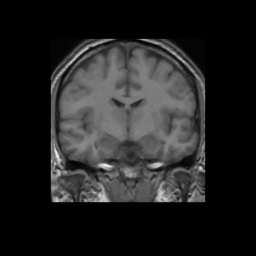

Accuracy is reported as Dice overlaps between a tool's segmentation and the Internet Brain Segmentation Repository (IBSR) manual segmentation for each of the 18 IBSR subjects. The inter-tool comparison (on the left below) shows the median Dice coefficient for each tissue class. The overlaps for FSL (from which the median values are drawn) are shown in the plot on the right.

Subject Accuracy (IBSR)

Overlap coefficients for each tissue class are shown here for each IBSR subject. Select a subject below to see the FSL results compared to other tools.